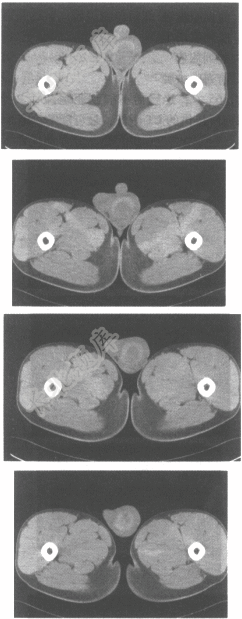

- 单项选择题男,20岁,外伤1天,左侧阴囊肿痛,结合CT平扫图像,最可能的诊断为

A、腹股沟疝

B、睾丸炎

C、睾丸血肿

D、睾丸囊肿

E、睾丸肿瘤